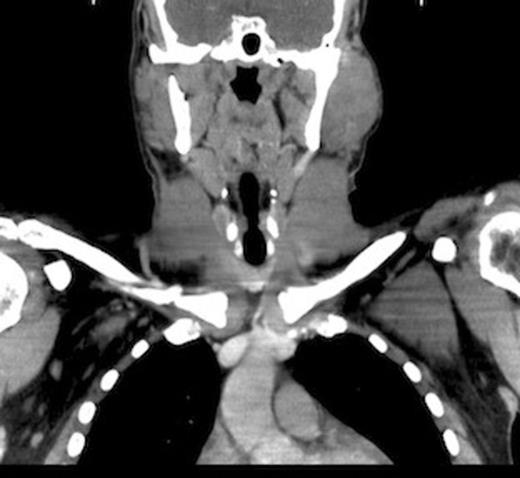

Postoperative prednisone taper treatment successfully decreased the size of the mass and was administered periodically as observation required. A repeat CT scan in July 2009 revealed a diffusely enlarged left parotid gland with complete resolution of the discrete mass (Fig.1–2). He was conservatively managed with periodic steroids until April 2010, when he complained of pain in the region and a feeling of gradual increase in size. A left parotidectomy was performed in May 2010, with removal of both the superficial and deep lobes of the parotid gland along with identification and preservation of the facial nerve.